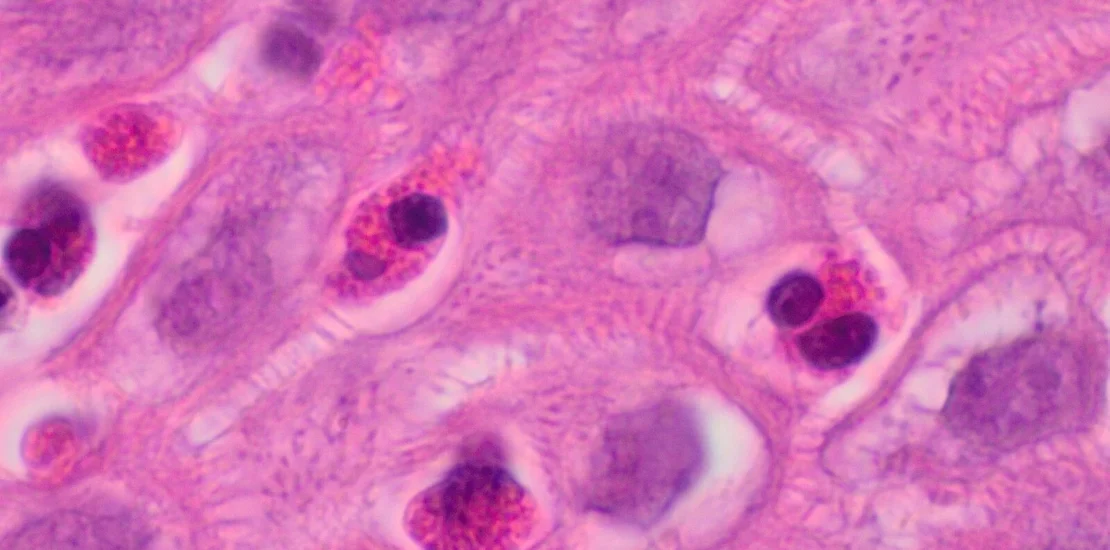

Un equipo de científicos de la Universidad de Tel Aviv ha anunciado un avance significativo en el tratamiento de la esofagitis eosinofílica (EoE), una enfermedad alérgica alimentaria crónica que ha ido en aumento en las últimas décadas.